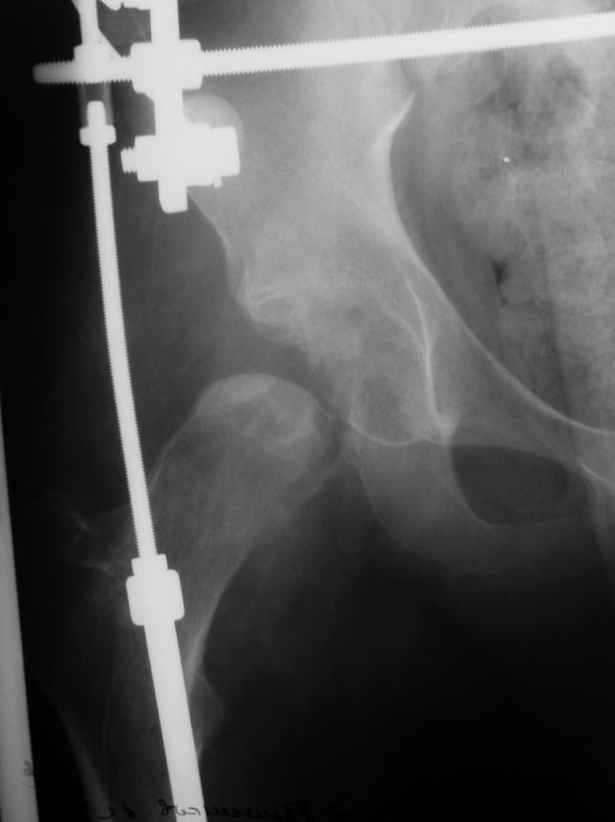

Здравствуйте. К нам поступил мальчик 15 лет с застарелым 7-месячным вывихом бедра из области. Травма мотоциклетная, при поступлении в больницу по месту жительства диагностирован перелом диафиза бедра и не распознан вывих бедра с этой же стороны.

Бедро было синтезировано пластиной и успешно срослось. Как поступить сейчас с вывихом? По КТ видны интерпонированные отломки, впечатление что это фрагменты головки бедра. Поделитесь, пожалуста, опытом. Спасибо.

What happened with femoral head?AVN?Plain x ray uncertain.

Фрагменты в проекции вертлужной впадины кажутся задненижним сектором голоки бедра